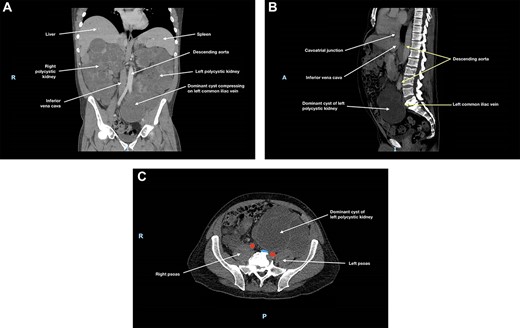

Ultrasound (US) and subsequent computed tomography (CT) of the abdomen and pelvis revealed compression of the left common iliac vein by a dominant cyst of the left polycystic kidney (Fig. 1), with extensive non-occlusive thrombus through to the left calf. There were also multiple hepatic cysts in both liver lobes, and the duodenal segments D1 and D2 had been displaced to the left, but there was no evidence to suggest bowel obstruction.

(A) Coronal, (B) sagittal and (C) axial views of the patient’s CT scan of his abdomen and pelvis at initial presentation; this showed enlarged polycystic kidneys, with the left kidney extending into the patient’s pelvis; there was compression of the left common iliac vein by a dominant cyst in the left polycystic kidney against the patient’s sacrum; in (c), the left common iliac vein is depicted in blue and the common iliac arteries are depicted in red; hepatic cysts and duodenal effacement are not visible in the selected planes; R, right; I, inferior; A, anterior; P, posterior.